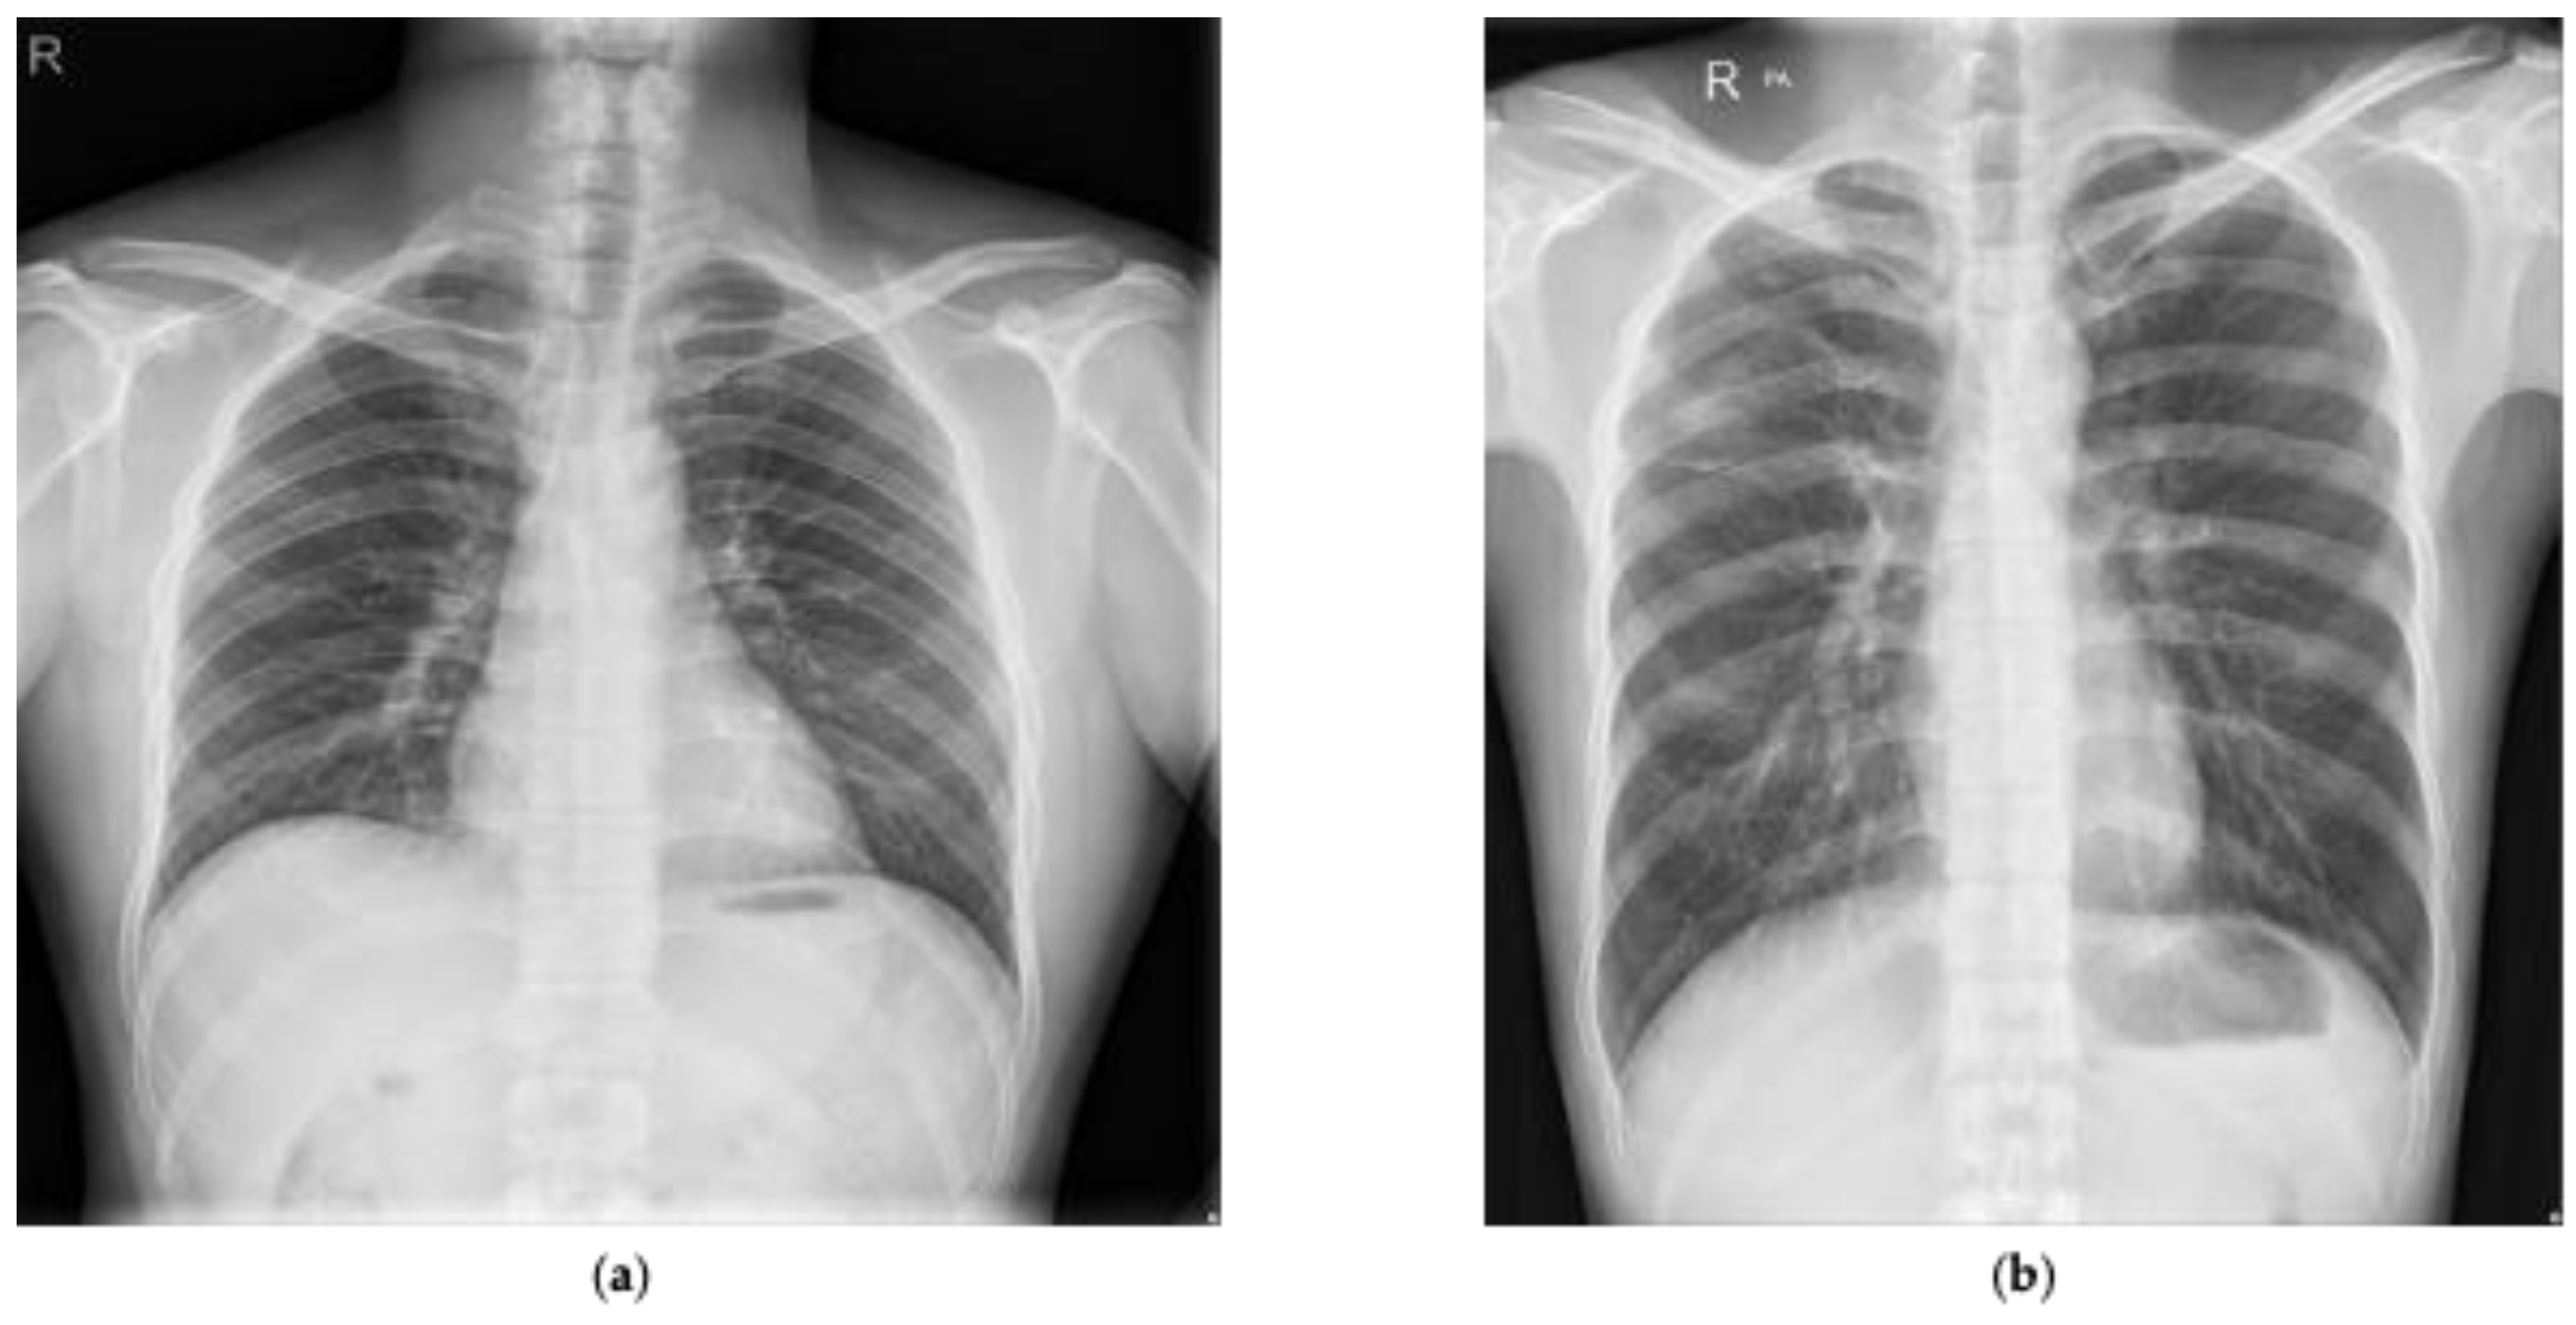

We also utilized a publicly available Shenzhen dataset marked by radiologists for the detection of tuberculosis [44,45,46,47]. This dataset was composed of 662 annotated chest radiographs with 336 marked as tuberculosis and the rest marked as normal. Figure 2 presents two examples presented in the Shenzhen dataset that have been marked as normal and tuberculosis, respectively, by radiologists. In addition, manual lung masks were publicly available for 566 cases in the Shenzhen dataset. Note that we included only those cases for this research.

Figure 2. Chest radiograph examples from the Shenzhen dataset marked by radiologists: (a) normal; (b) tuberculosis.